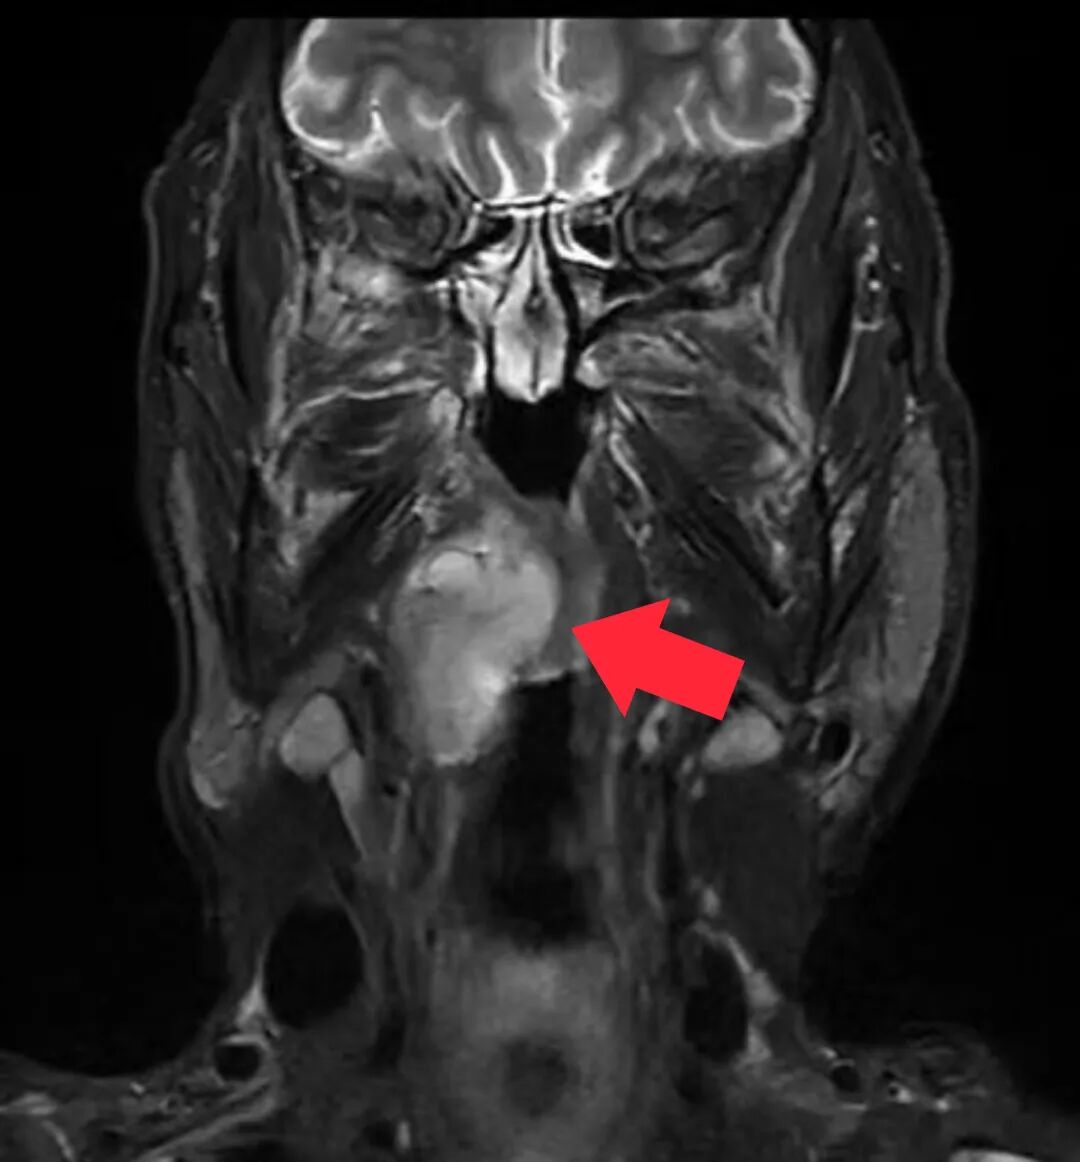

2周期后,检查结果显示肿瘤明显缩小,这给叶大叔后续治疗增加了很大信心,但邓泽义主任医师指出,仅仅依赖“化疗”,肿瘤无法完全消退。

△新辅助化疗2周期后